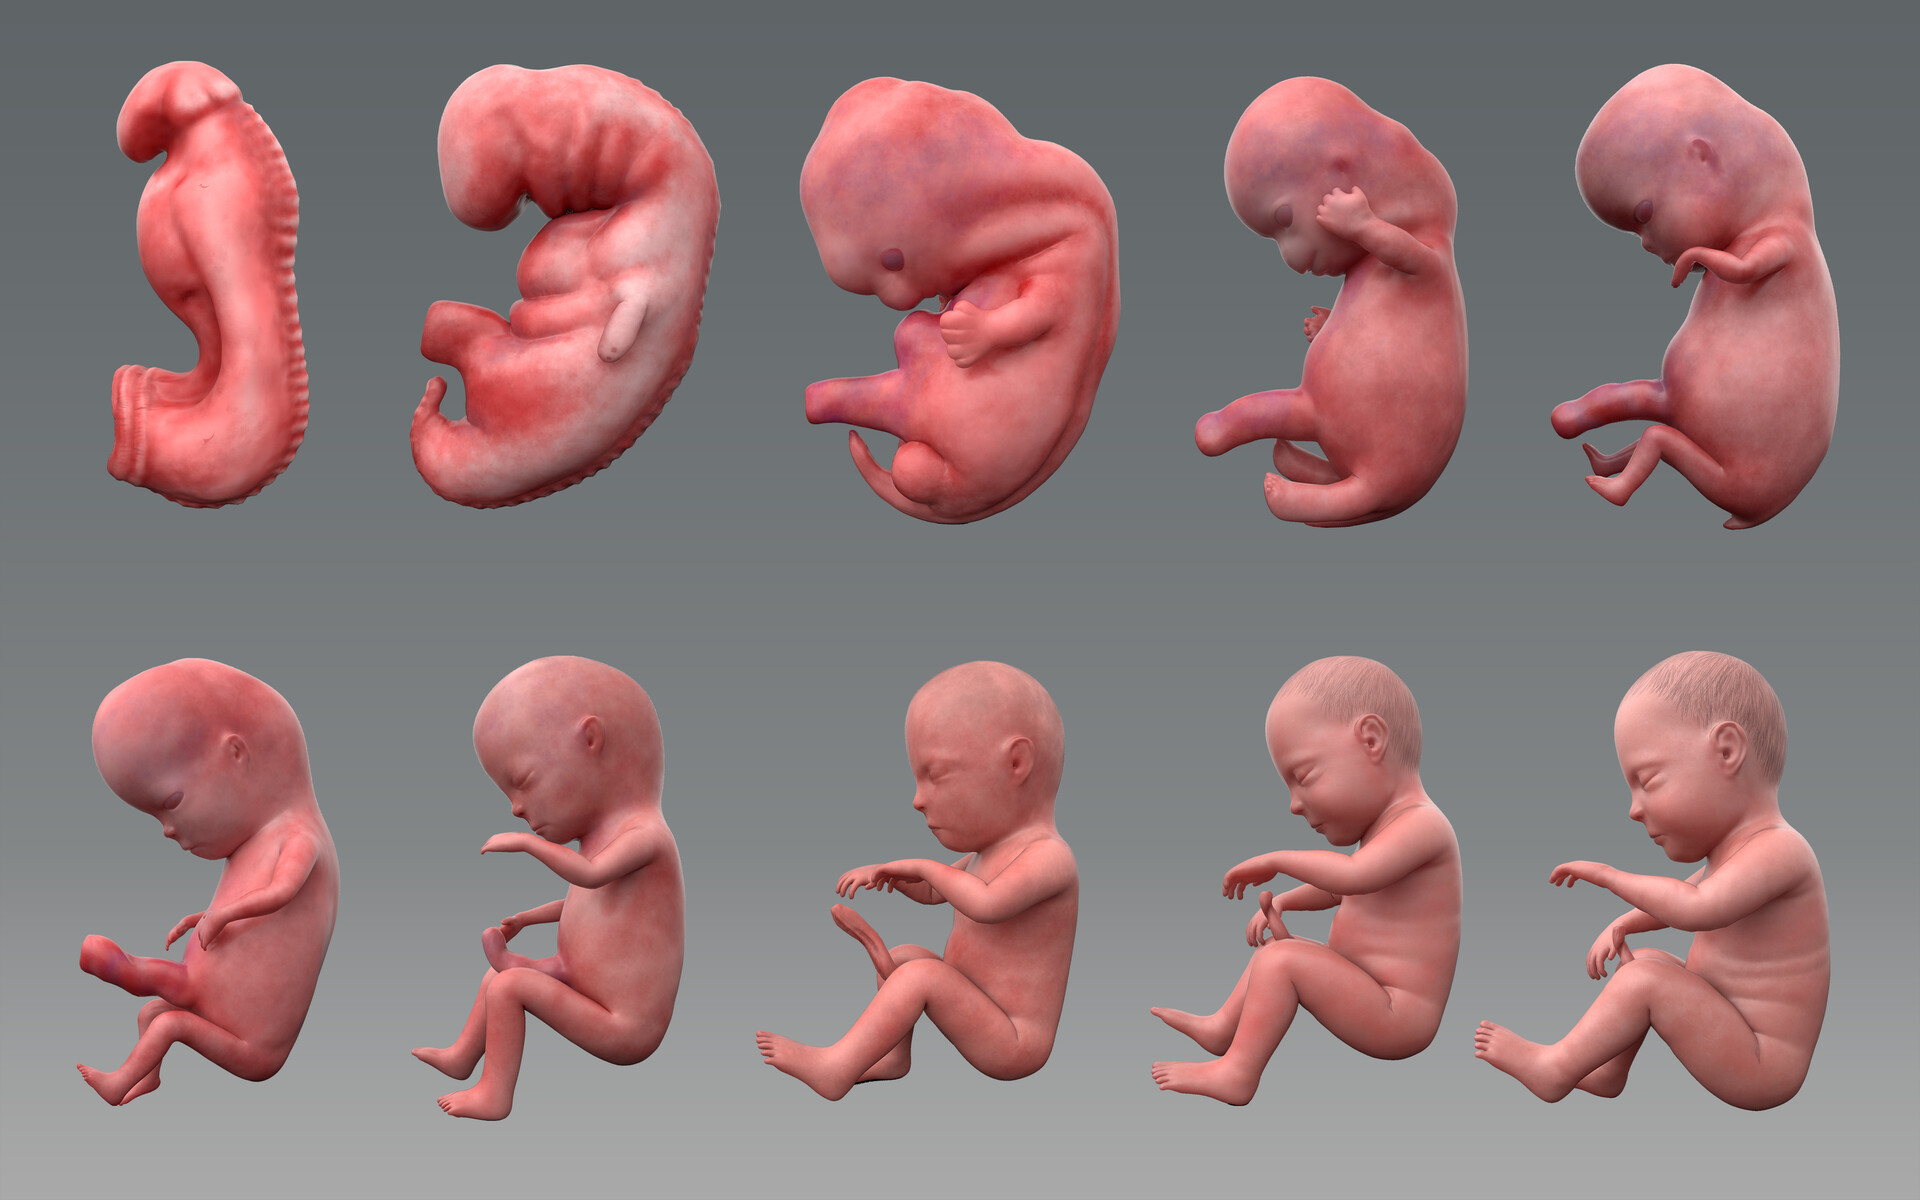

Pin On Fetus

Pin On Fetus

Fetal Development Middlesex London Health Unit

Fetal Development Middlesex London Health Unit

Fetal Development Pictures